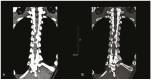

The focal calcification or ossification of the ligamentum flavum is a rare cause of thoracic myelopathy and most often occurs among individuals of Japanese descent. It is rare in other ethnic groups and in individuals below the age of 50. It is most often described at the lower thoracic level, being uncommon in the lumbar region and rare in the cervical region. Here, we present the case of a 44-year-old White female patient who sought medical attention with an eight-month history of paraesthesia of the lower limbs and progressive difficulty in walking. The clinical profile, together with computed tomography and nuclear magnetic resonance imaging of the spine, led to a diagnosis of compressive thoracic myelopathy due to ossification of the ligamentum flavum in the thoracic and lumbar spine. The patient underwent laminectomy and dissection of some of the affected ligamentum flavum, without any intraoperative complications. After three months of clinical follow-up, the patient had progressed favorably, having no sensory complaints and again becoming ambulatory.